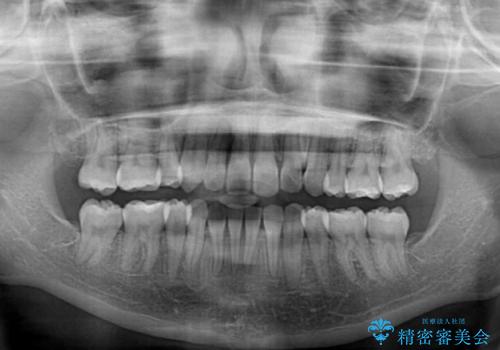

- 前歯のデコボコやクロスバイトと上顎の前突感による口の閉じにくさを気にして来院された患者様です。

目立たない装置を希望されたので、上顎が裏側装置のハーフリンガルを選択し、上下左右の小臼歯(計4歯)を抜歯して矯正治療を行うこととしました。

表側のワイヤー矯正に比べると治療期間は長く、費用も高額となりますが、どうしても目立たせたくないという方にはお勧めの抜歯矯正です。